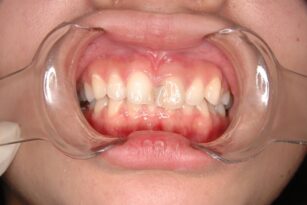

審美・補綴歯科

2025年12月05日

前歯の色が気になる 20代 女性 ジルコニアクラウンの症例